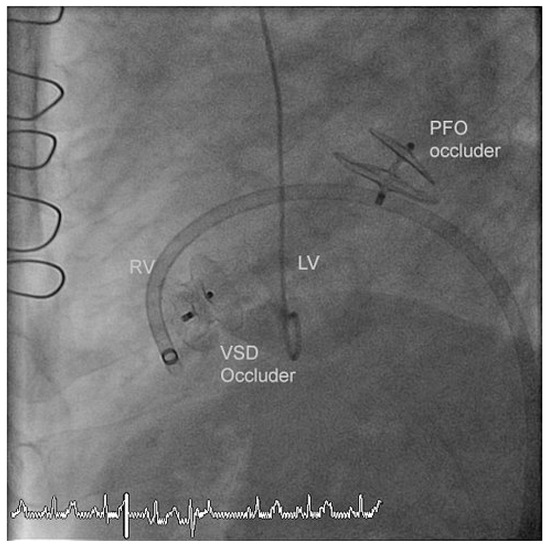

A Case for Incidental Coronary Angiography During Percutaneous Closure of the Patent Foramen Ovale?

by Nikesh Raj Shrestha, Thomas Pilgrim, Alexander Kadner and Bernhard Meier

Cardiovasc. Med. 2011, 14(10), 283; https://doi.org/10.4414/cvm.2011.01616 - 26 Oct 2011

A 42-year-old male had undergone a successful closure of a patent foramen ovale (PFO) seven years earlier for cryptogenic stroke. In spite of several risk factors an incidental coronary angiogram was not performed due to his young age (35 years at that time). [...] Read more.

A 42-year-old male had undergone a successful closure of a patent foramen ovale (PFO) seven years earlier for cryptogenic stroke. In spite of several risk factors an incidental coronary angiogram was not performed due to his young age (35 years at that time). Seven years later a myocardial infarction (MI) caused an apical ventricular septal defect (VSD) necessitating a surgical correction. Finally device closure became necessary due to patch dehiscence. Incidental coronary angiography on the occasion of PFO closure would have resulted i n timely coronary treatment by acetylsalicylic acid and a statin and perhaps coronary angioplasty. The MI and its complicated course could most likely have been prevented. Full article

Show Figures

Figure 1